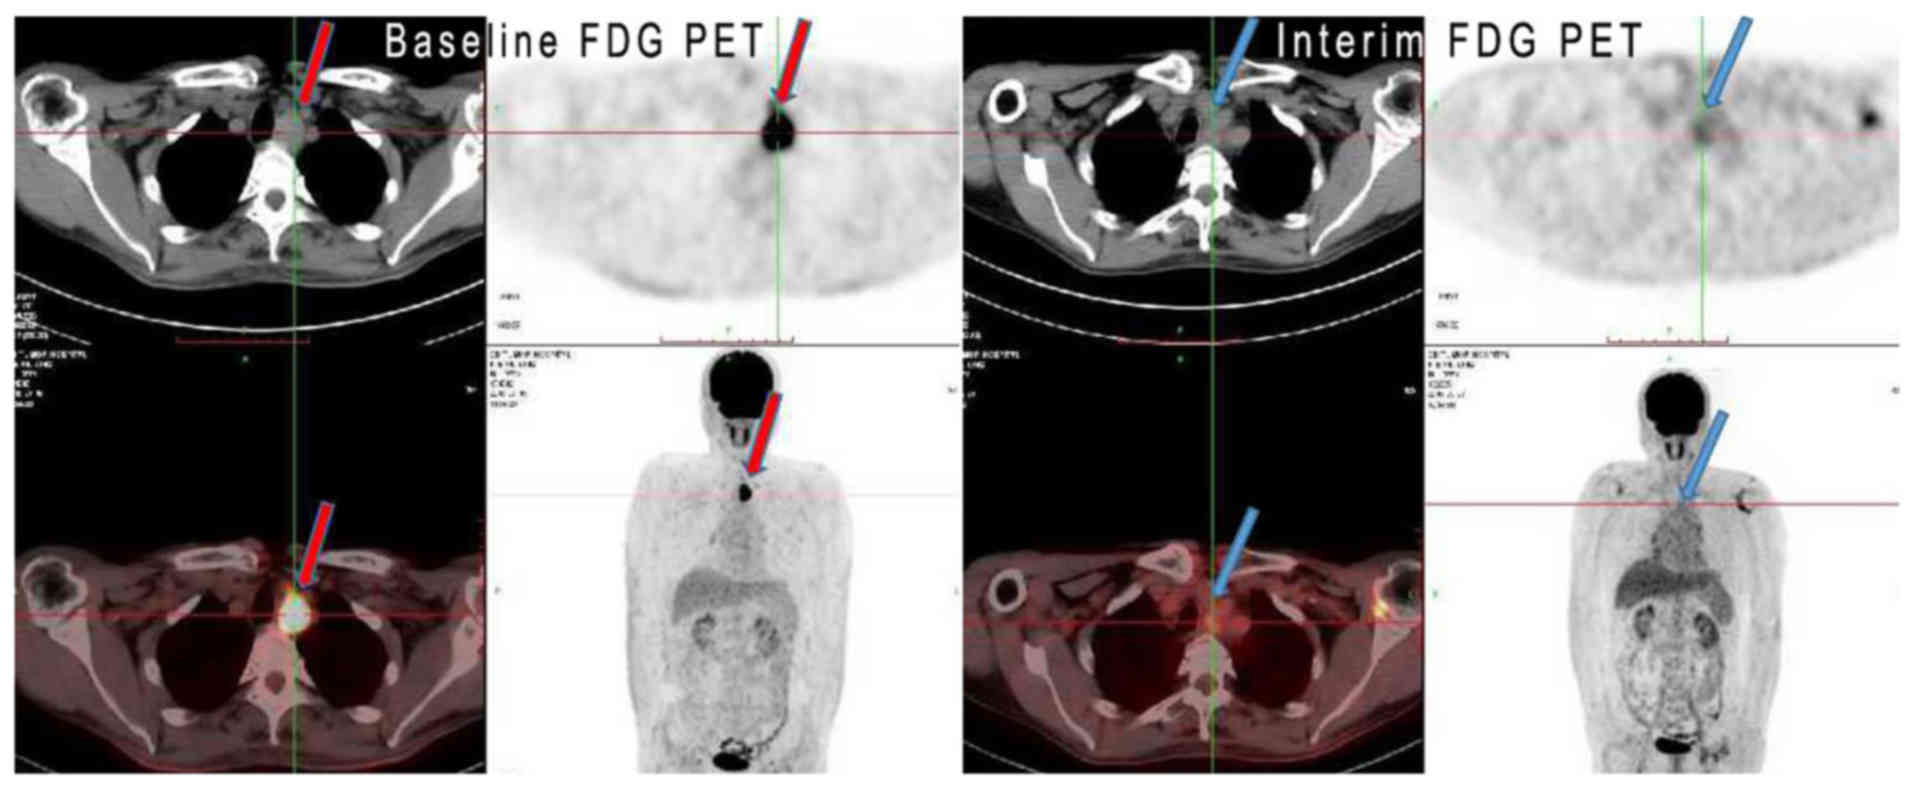

Petct can detect esophageal cancer determine if it has spread assess the effectiveness of a treatment plan and determine if the cancer has returned after treatment. Combining a pet scan with an mri or ct scan can help make the images easier to interpret. A positron emission tomography pet scan detects abnormal cell metabolism to diagnose cancer heart disease and brain disorders before other tests can.

A biopsy is the removal of tissue in order to examine it for disease. So petct is a relatively new very powerful imaging methodology for the diagnosis and staging of a wide range of cancers including esophageal cancer. It can help doctors work out whether tissue is active cancer or not.

Correct integration of petct into the conventional work up of esophageal cancer requires a multidisciplinary approach that combines the information from petct with results of clinical assessment diagnostic ct. For the prevention and early detection of cervical cancer. Petct scans can be useful.